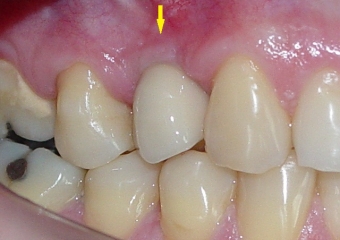

Prótese fixa em porcelana

Imagem aproximada da prótese fixa em porcena instalada